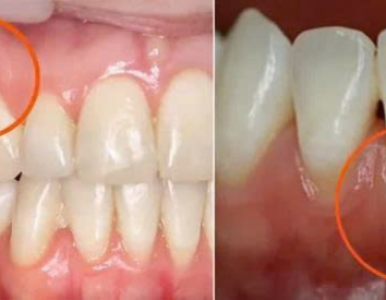

Tụt nướu (tụt lợi) gây lộ chân răng, ê buốt, mất thẩm mỹ và nguy cơ mất răng. Tìm hiểu nguyên nhân, phương pháp điều trị tụt nướu – viêm nha chu và bảng giá chi tiết tại Nha Khoa SV.

Tụt lợi có chữa được không? Bài viết phân tích nguyên nhân, hậu quả và các phương pháp điều trị hiện đại tại Nha khoa SV – 99 Cao Thắng, Phường Bàn Cờ, TP.HCM. Có video hướng dẫn và tư vấn chi tiết.